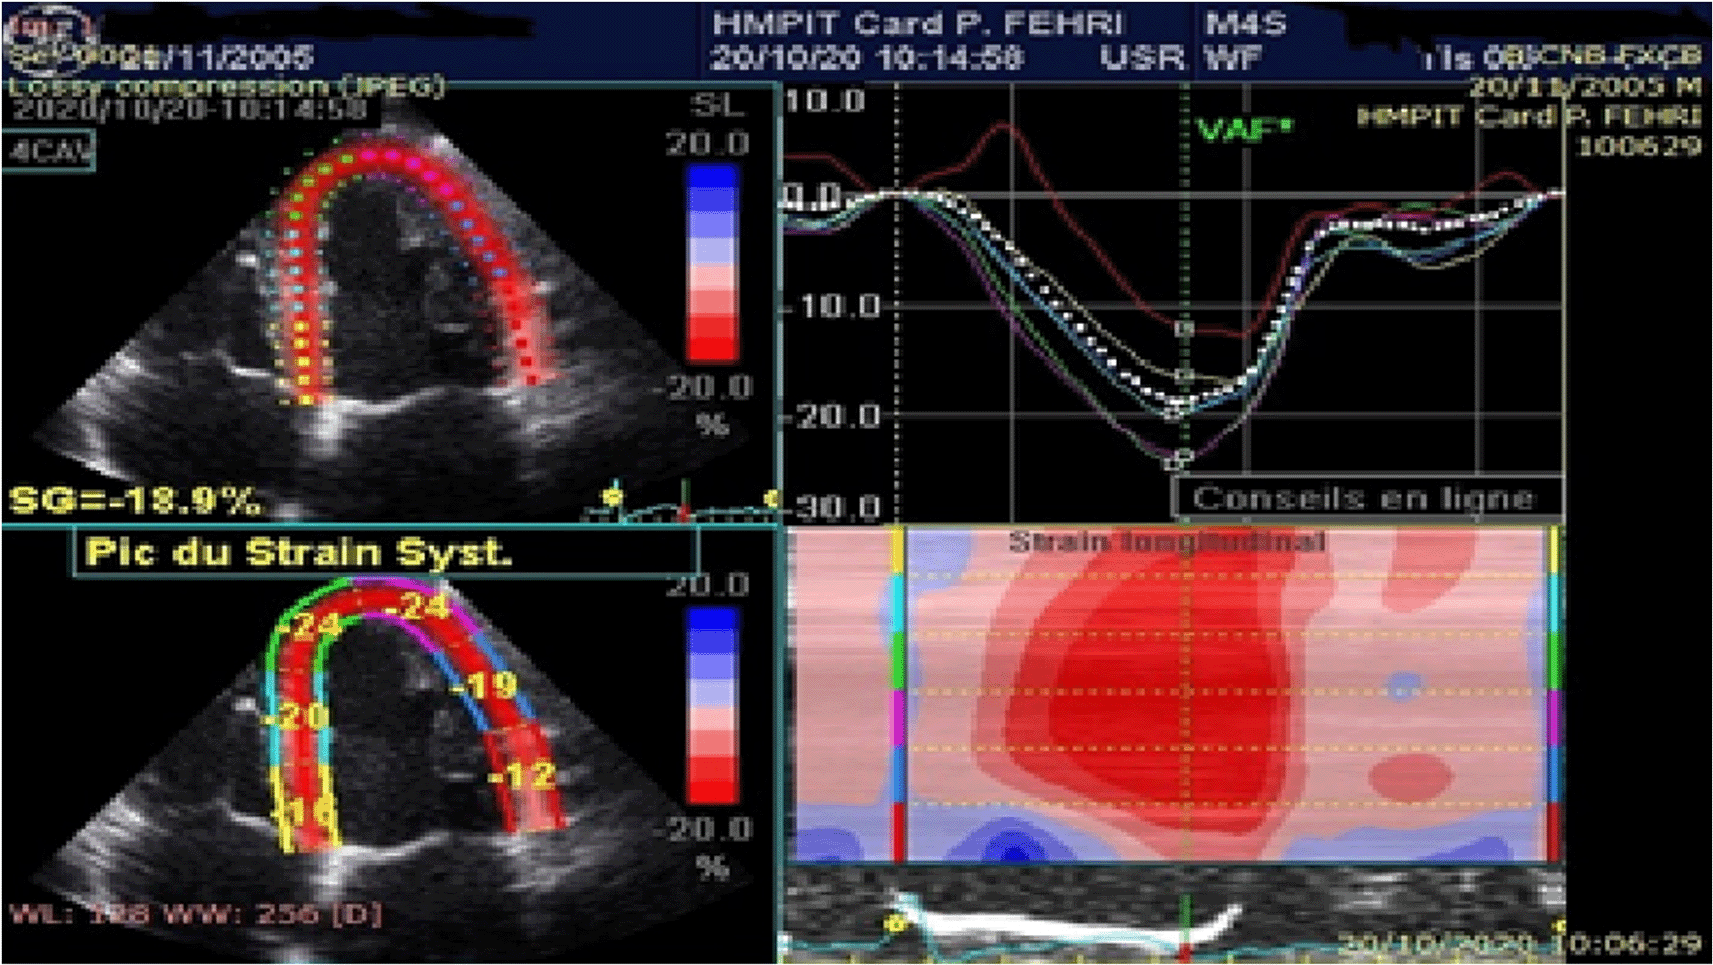

The quality of myocardial tracking was visually checked in real time then manually corrected to ensure optimal tracking. The software then tracks the deformation of the myocardium during cardiac cycle to calculate peak systolic segmental strain. Global longitudinal strain (GLS) is determined as the average of the segmental strains (Figures 1, 2).

Study of longitudinal myocardial deformation using the speckle tracking technique

The measurement of the left ventricular global longitudinal strain LVGLS showed a mean value of -21.2±3% in the SCA group.

The GLS was impaired in 46% of cases for a reference threshold of -20%.

The comparative study between the two groups of patients showed a statistically significant difference with a mean value in SCA group of -21.22±3%, compared to -25.03±2.9% in C group (p<0.01) (Figure 3).